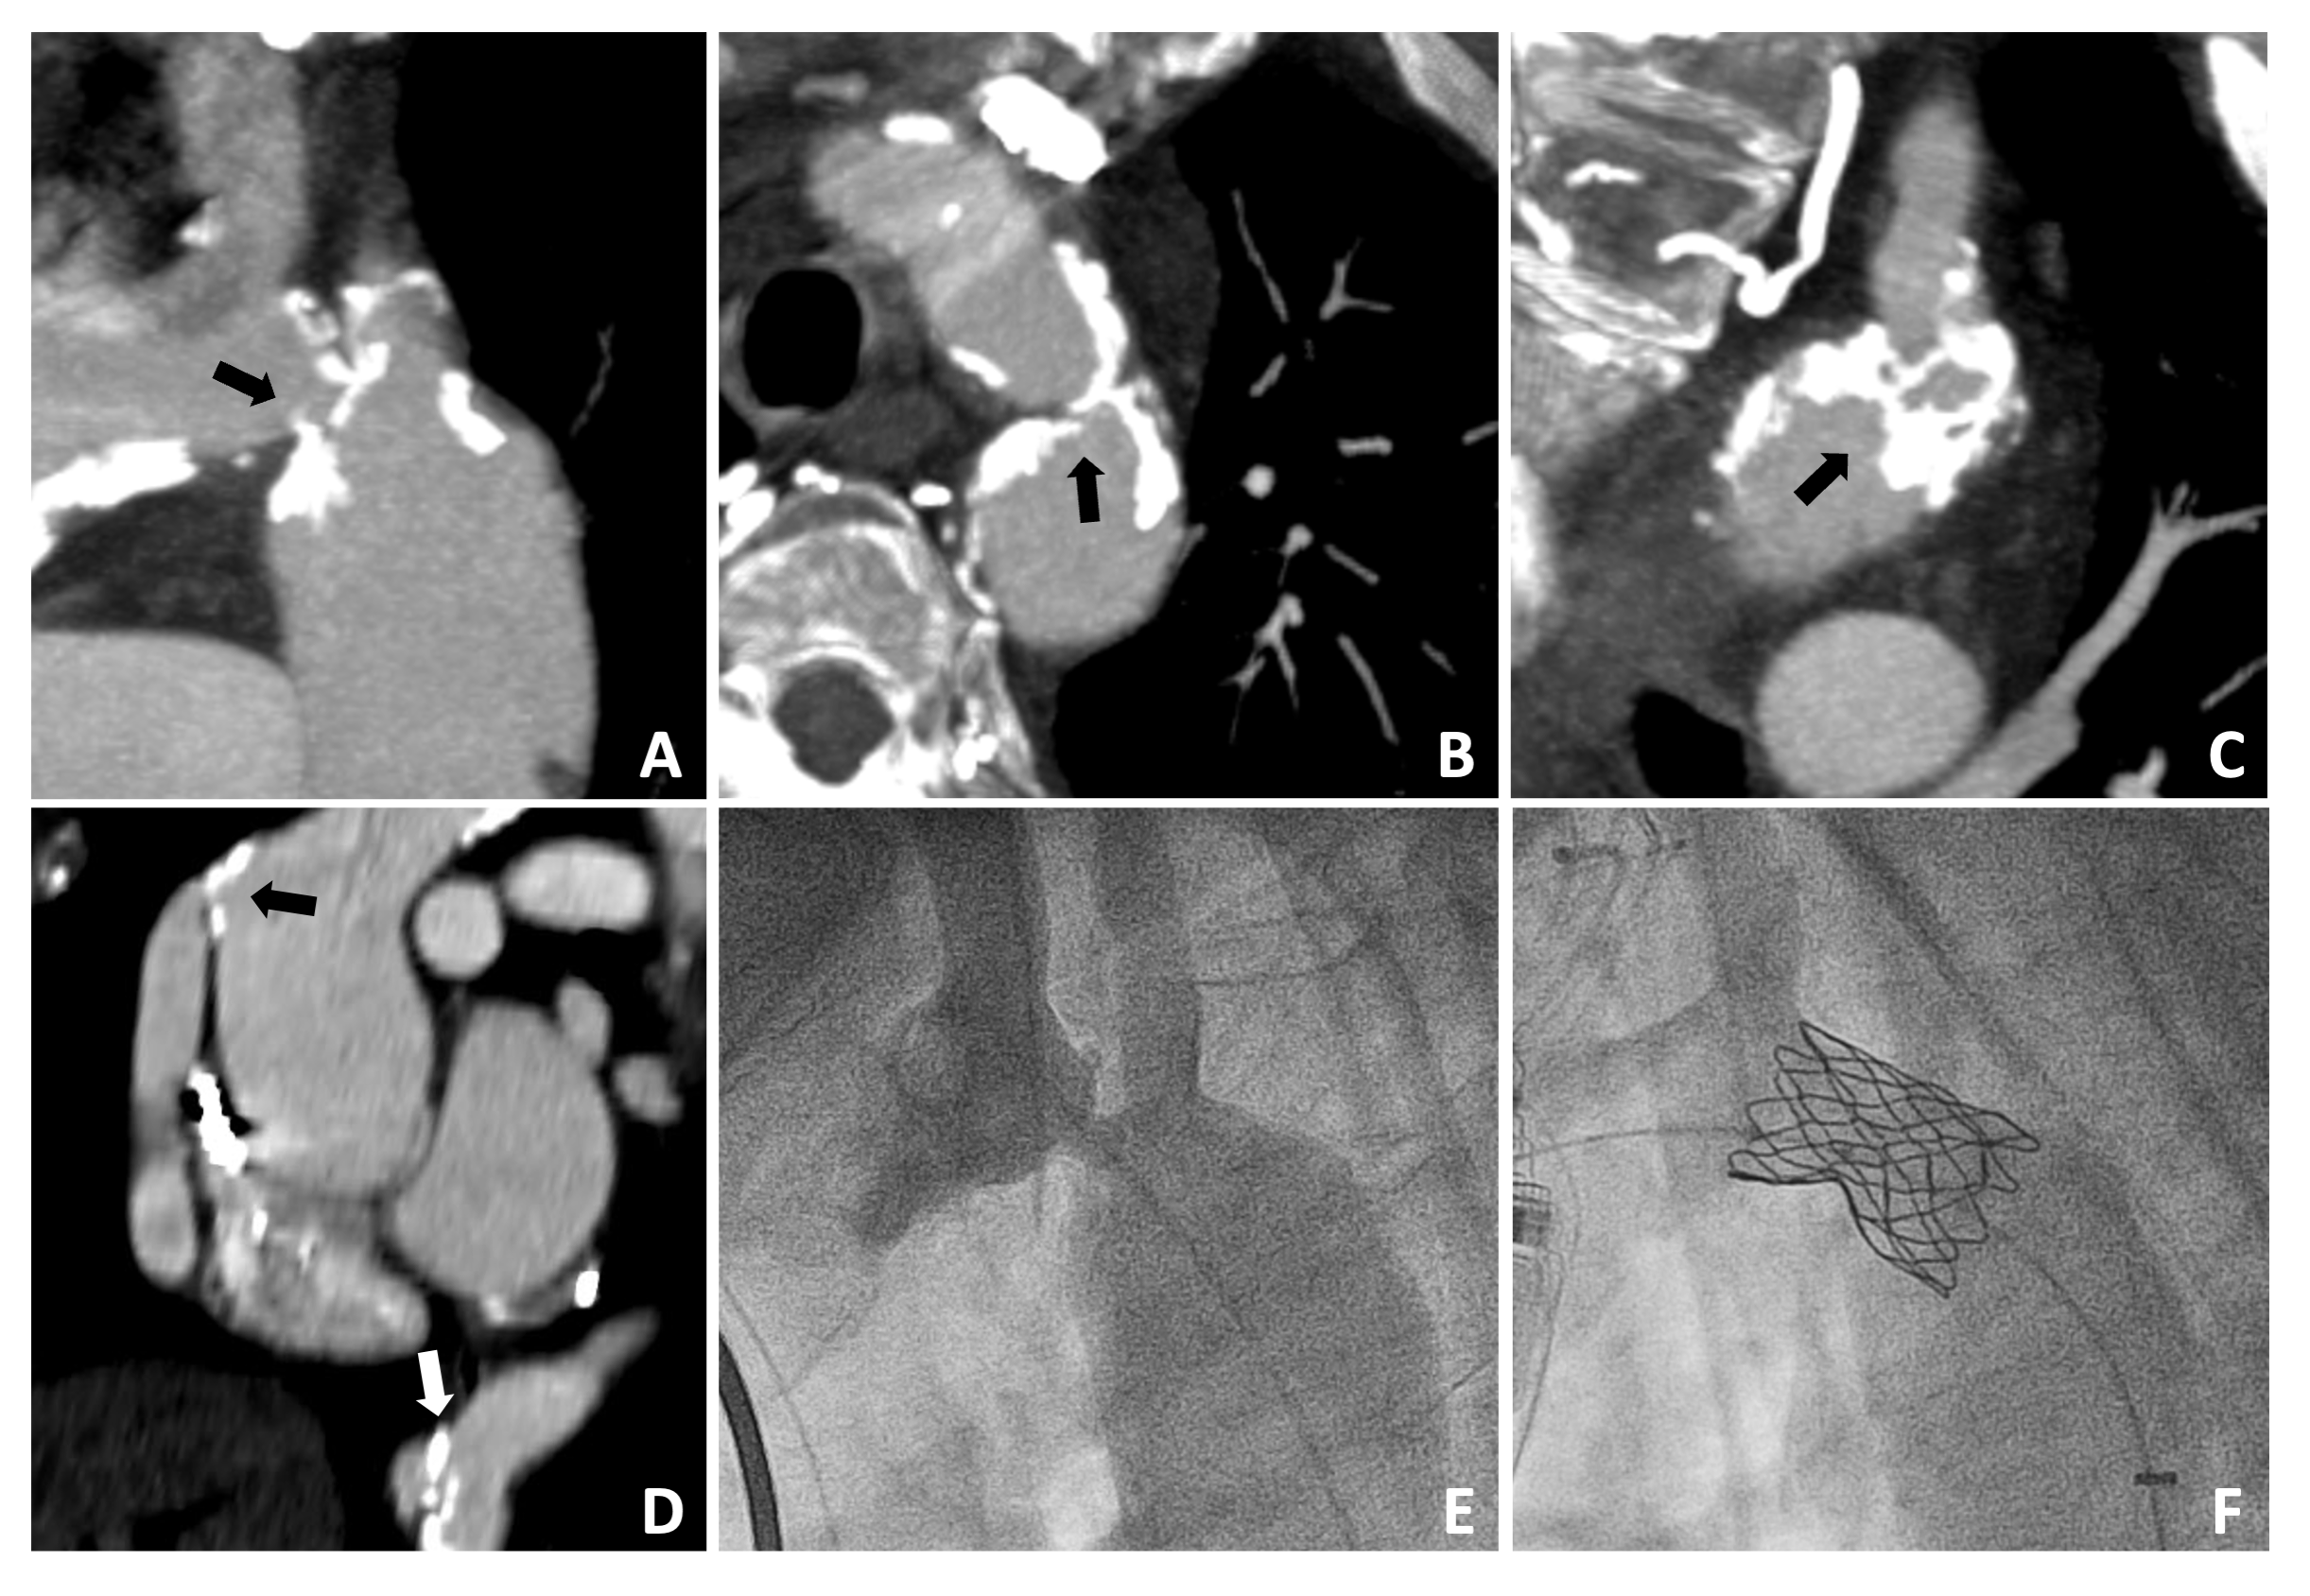

A 38-year-old man with a history of congenital aortic valve stenosis status post-Ross procedure with a 24-mm RV-PA homograft at the age of 15. He was lost to follow-up for many years, returning to care in the setting of new onset atrial flutter. At that time, he was discovered to have mixed conduit disease by echocardiography with a mean gradient of 36 mm Hg and moderate regurgitation with mild right ventricular dysfunction, prompting referral for transcatheter conduit rehabilitation. A pre-procedure CTA revealed heavy circumferential calcifications with a minimum luminal diameter of 14 mm (Figure 4A-C).

Like Patient 3, there was concern over both conduit fracture with angioplasty prior to covered stent implantation and inability to adequately relieve the outflow tract gradient with stenting and angioplasty alone. Therefore, IVL-assisted conduit stenting was performed up front. Coronary angiography demonstrated a remote position from the RV-PA conduit, and coronary compression testing was not performed. A 12 x 30-mm Shockwave lithotripsy balloon was advanced over an 0.018-inch wire and into the RV-PA conduit. Given a minimum luminal area of greater than 12 mm, an 8 x 40-mm Armada balloon (Abbott) was advanced into the conduit over a 0.035-inch wire alongside the IVL balloon to ensure its adequate apposition to the vessel wall. A total of 150 pulses were delivered in 30 pulse increments, allowing intermittent systemic pressure recovery. A 3.9-cm CCPS stent followed by a Palmaz XL 4010 stent was deployed within the conduit over 18-mm balloons inflated to 6 atm. Post-dilation was carried out with a 24-mm Atlas Gold balloon to 8 atm, fully expanding the stent complex. A Melody valve was implanted within the stented conduit on a 22-mm Ensemble Delivery system with a reduction in the conduit gradient from 70 to 6 mm Hg. Final angiography showed no evidence of conduit disruption (Figure 4D). There were no procedural complications, and the patient was discharged within 24 hours.